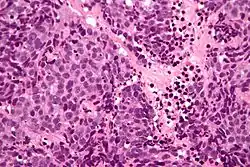

| Micrograph of a sinonasal undifferentiated carcinoma. H&E stain. | |

Low mag. -

High mag.